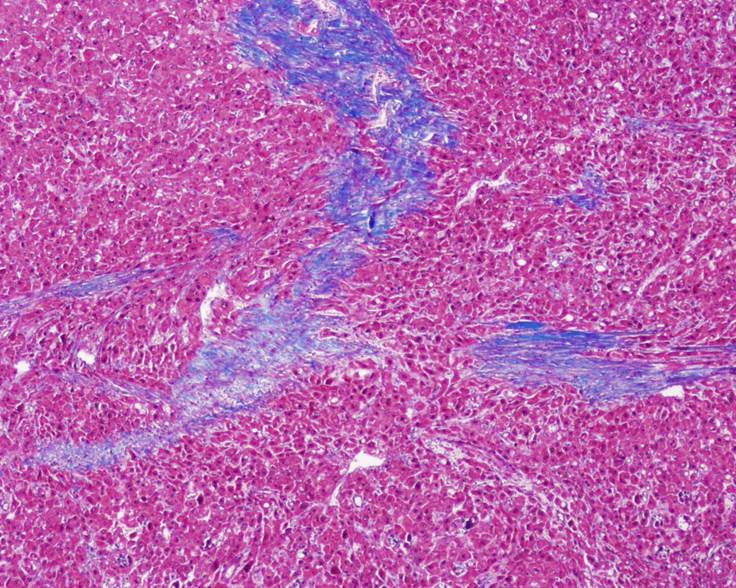

Respecto a las ayudas imagenológicas, se realizó una tomografía simple de cráneo que evidenció lesiones focales hipodensas en sustancia blanca periventricular de aspecto inespecífico sin efecto de masa (Figura 1); dado que estos hallazgos no descartaron neuroinfección, se llevó a cabo un estudio de líquido cefalorraquídeo que no reportó alteraciones. Posteriormente, se ordenó una resonancia magnética nuclear de abdomen que detectó hígado aumentado de tamaño y disminución de la intensidad de señal de manera difusa por infiltración de grasa hepática; además, en el segmento VIII se observó lesión focal hepática hipervascular de contornos lobulados, forma irregular y diámetro de 13x11x13 cm, con compresión de venas suprahepáticas, vena cava inferior y vena porta intrahepática izquierda con compresión de la vía biliar intrahepática (Figura 2). Dado el hallazgo de masa hepática, se decidió tomar biopsia de la lesión, cuyo reporte histopatológico fue compatible con FL-CHC (Figura 3).

Figura 3 Biopsia hepática de carcinoma fibrolamelar.

Las causas de un shunt portosistémico pueden estar relacionadas con su ubicación intrahepática o extrahepática, pero en su mayoría son congénitas con manifestaciones tempranas. Otras causas incluyen lesión hepática hipervascular con o sin efecto oclusivo venoso, para lo cual la biopsia hepática en el abordaje diagnóstico descarta cirrosis, esquistosomiasis o granulomas9. El FL-CHC es un tipo histológico del carcinoma hepatocelular (CHC) que representa el 1 % de tumores primarios hepáticos, con incidencia de 0,02 casos por cada 100.000 habitantes10, y es causado por la mutación DNAJB1-PRKACA en el cromosoma 19 con delección de 8 genes, siendo los más comunes MUC4 (asociado a otros tumores gastrointestinales) y GOLCA6L2. El mecanismo de tumorigénesis en el FL-CHC ha sido un misterio desde su identificación inicial en 1956; sin embargo, se han logrado avances importantes tras el descubrimiento de la mutación DNAJB1-PRKACA hecho por Honeyman et al.11 en 2014. La prevalencia de esta mutación en prácticamente todas las muestras de FL-HCC, junto con un genoma relativamente estable, sugiere fuertemente que la proteína de fusión es un impulsor primario de este tipo de cáncer10. Su presencia es mayor en adultos jóvenes con edad media de presentación a los 25 años, sin diferencia de género y con marcadores tumorales negativos; además, es responsable de hasta el 9 % de los tumores hepáticos con compromiso del 66 % del lóbulo hepático izquierdo y con descripción de asociación con hiperamonemia5,12,13.

En el proceso de entender la fisiopatología de la hiperamonemia, el FL-HCC se relaciona con el efecto de una lesión hepática hipervascular grande con presencia de shunt que disminuye el aclaramiento de productos nitrogenados8,12. En la presentación del caso reportado se observa una masa con gran ocupación del lóbulo hepático derecho y presencia de oclusión venosa como causa de hiperamonemia debido a shunt portosistémico, lo cual se evidenció al descartarse las otras etiologías y al evidenciarse la mejoría luego del trasplante hepático.